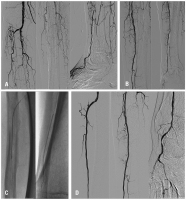

Claudicatio intermittens

Abbildung 1: A. Patient mit ausgeprägter Claudicatio intermittens im linken Unterschenkel und Fuß (Gehstrecke 50 Meter) bei subtotaler Stenose des Truncus tibiofibularis und der proximalen A. tibialis anterior. B. Beschwerdefreiheit nach PTA und Stentimplantation